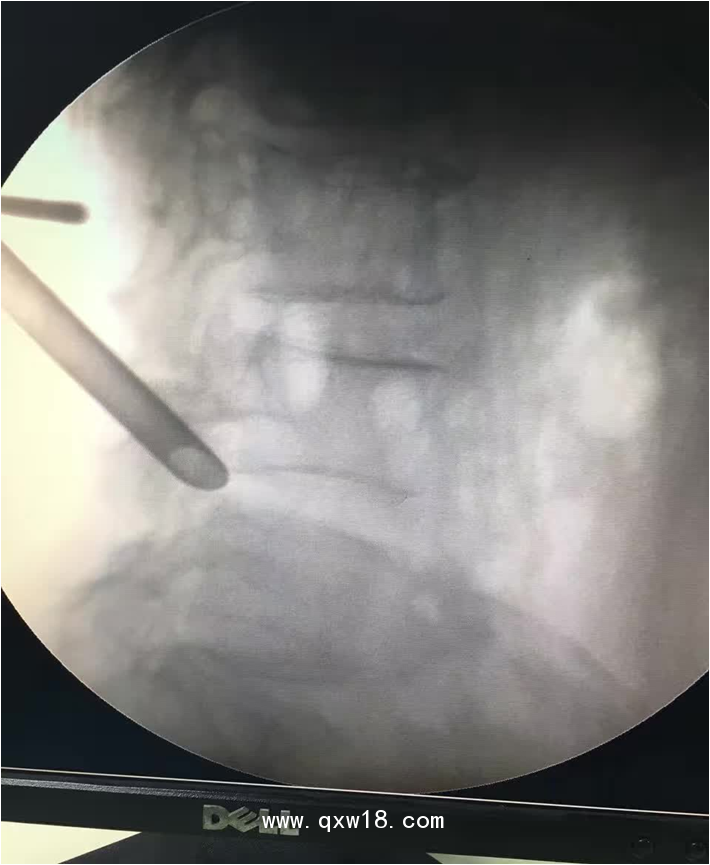

椎間孔鏡品牌椎間孔鏡椎間孔鏡技術(shù)椎間孔鏡培訓(xùn)產(chǎn)品說明:

portant; word-wrap: break-word !important;">椎間孔鏡手術(shù)圍手術(shù)期注意事項:

portant; word-wrap: break-word !important;">一、 術(shù)前常規(guī)注意事項:1?排便應(yīng)通暢,腸腔脹氣,便秘等,嚴(yán)重影響到術(shù)中操作必須的C臂透視的效果。用力排便等將在術(shù)后由于腹壓的增高,而容易導(dǎo)致髓核從修復(fù)的纖維環(huán)破口內(nèi)突出,導(dǎo)致手術(shù)失敗。2?術(shù)前停止服用活血等藥物。如丹參、紅參等。服用阿司匹林的患者需要停藥5天后方才安排手術(shù)。3?由于腰椎局麻手術(shù),不需要全麻,故術(shù)前不需禁食,但術(shù)前一餐也不能飽食,部分患者術(shù)中需靜脈用藥輔助,可能因此引起惡心、嘔吐等反應(yīng)。4?術(shù)前患者應(yīng)配備合適的腰圍并帶進(jìn)手術(shù)室,術(shù)后即刻就需帶上。腰圍寧緊勿松,寧硬勿軟。